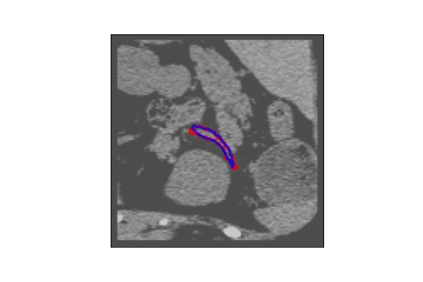

The human annotations are imperfect, especially when produced by junior practitioners. Multi-expert consensus is usually regarded as golden standard, while this annotation protocol is too expensive to implement in many real-world projects. In this study, we propose a method to refine human annotation, named Neural Annotation Refinement (NeAR). It is based on a learnable implicit function, which decodes a latent vector into represented shape. By integrating the appearance as an input of implicit functions, the appearance-aware NeAR fixes the annotation artefacts. Our method is demonstrated on the application of adrenal gland analysis. We first show that the NeAR can repair distorted golden standards on a public adrenal gland segmentation dataset. Besides, we develop a new Adrenal gLand ANalysis (ALAN) dataset with the proposed NeAR, where each case consists of a 3D shape of adrenal gland and its diagnosis label (normal vs. abnormal) assigned by experts. We show that models trained on the shapes repaired by the NeAR can diagnose adrenal glands better than the original ones. The ALAN dataset will be open-source, with 1,594 shapes for adrenal gland diagnosis, which serves as a new benchmark for medical shape analysis. Code and dataset are available at https://github.com/M3DV/NeAR.